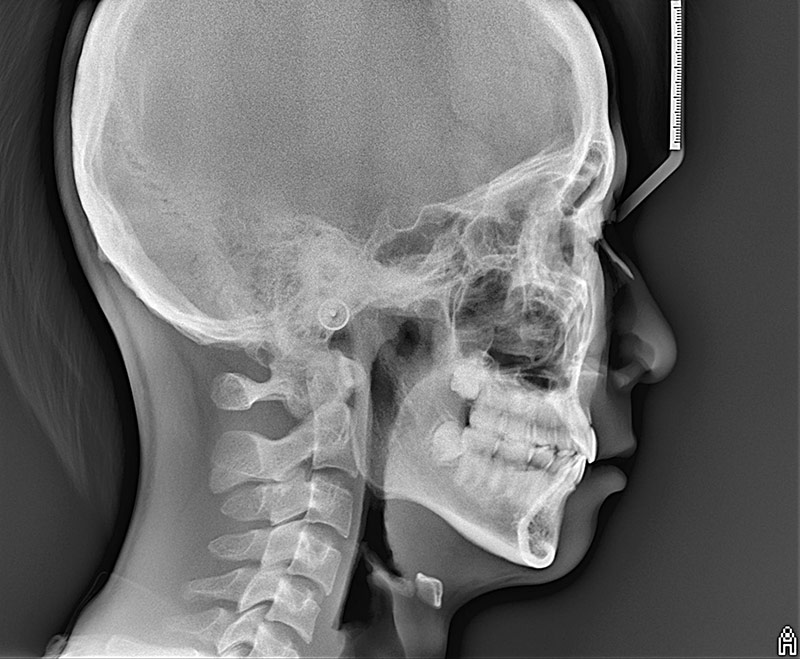

セファログラム(頭部X線規格写真)撮影装置は、矯正治療に不可欠な撮影機器です。

セファログラムとは、ある一定の規格に則ったレントゲン写真で、顔の側面や正面を撮影し、上顎と下顎のバランスやズレ、顎の形、歯の傾き方、顔面全体と口元のバランスなどが診断できます。

セファログラムから得られた情報がなければ、治療計画を立てることができません。

セファログラム

セファログラムから得られた情報結果は、ポリゴン表やプロフィログラムといった分析により、治療前・中・後の治療方針の一助とします。

つまり、矯正歯科医にとって、セファログラムなくして矯正治療を行うことはありません。

また、矯正専門医はセファログラムから得られた知見を患者様に提示し、説明します。